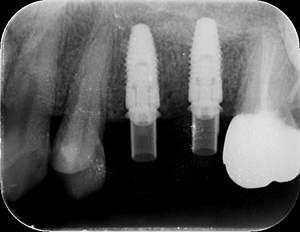

インプラント治療の症例2

レントゲン写真

- Befor

- After

| 年齢 | 50代・男性 |

|---|---|

| 主訴 | 左上7番 左下5番7番 |

| 治療内容 | ・インプラント埋入 ※1:GBR(骨造成)・・・骨再生誘導法。骨の高さや厚みを人工骨や人工膜などを使用し再生する方法 |

| 治療費 | 合計:1,809,500円(税込) ■内訳 ・左上7番 ・左下5番7番 |

| 治療期間 | 左上7番約1年 左下5番7番約10ヵ月 |

| 治療方針 | 左上7番は昔他院で被せものをしており、被せものの中が歯ぐきの中まで虫歯になっていたため抜歯せざるを得ない状態だった。抜歯と同時に骨造成を行い、骨が出来るまで4ヵ月待ってからインプラントを埋入した。 ※2ポンティック・・・歯のない部分を補うダミーの歯。 |

| 担当者所見 | 元々金属の被せものが多く入っていたため、2次カリエス※3が多かった。今回は金属ではなく、ジルコニアを使用し、2次カリエスにならないよう、患者様にはブラッシング指導とメンテナンスの重要性をお伝えした。 ※3二次カリエス・・・詰め物や被せものを入れた歯が虫歯になること。 |